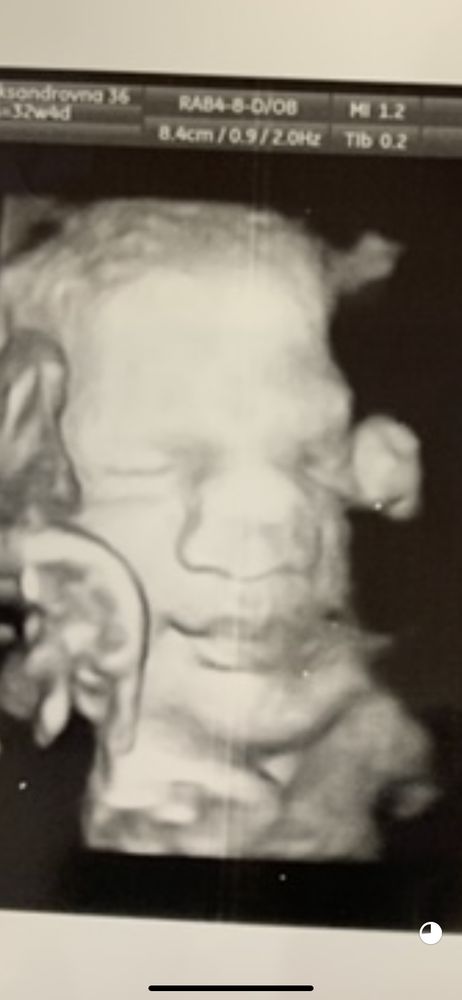

Странный носик на узи

Он расплющен ))) уперся во что то . Мы по узи ждали боксера с кривым носом , а родился мини носик Изображение

Хороший носик, уперся в плаценту, если вы лицом в подушку ляжете, такой же будет

Хороший носик, уперся во что то и сплющился немного)

Ой ,у нас такой же на узи на 3 скриненге был😁 просто ребеночку тесно уже .